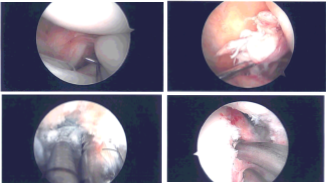

Examination of the knee showed a bucket handle medial meniscus tear right from the posterior horn to the mid body. It also showed avulsion and injury to the ACL with collapse. The lateral compartment showed no tear or injury. Patellofemoral compartment was normal. We decided to harvest the quadriceps autograft as was planned.

Intraoperative Arthroscopy Images

In the meantime, an arthroscope was inserted into the knee again. Inside out repair of the medial meniscus was planned using zone-specific cannulas from the meniscus were used. Sequential from the posterior horn to the mid body. All the needles were retrieved out of the medial knee.

The needles were cut and the sutures were held by a hemostat. ACL debridement was performed. The femoral attachment of the ACL was prepared using the shaver. Tibial attachment was also prepped using the shaver.